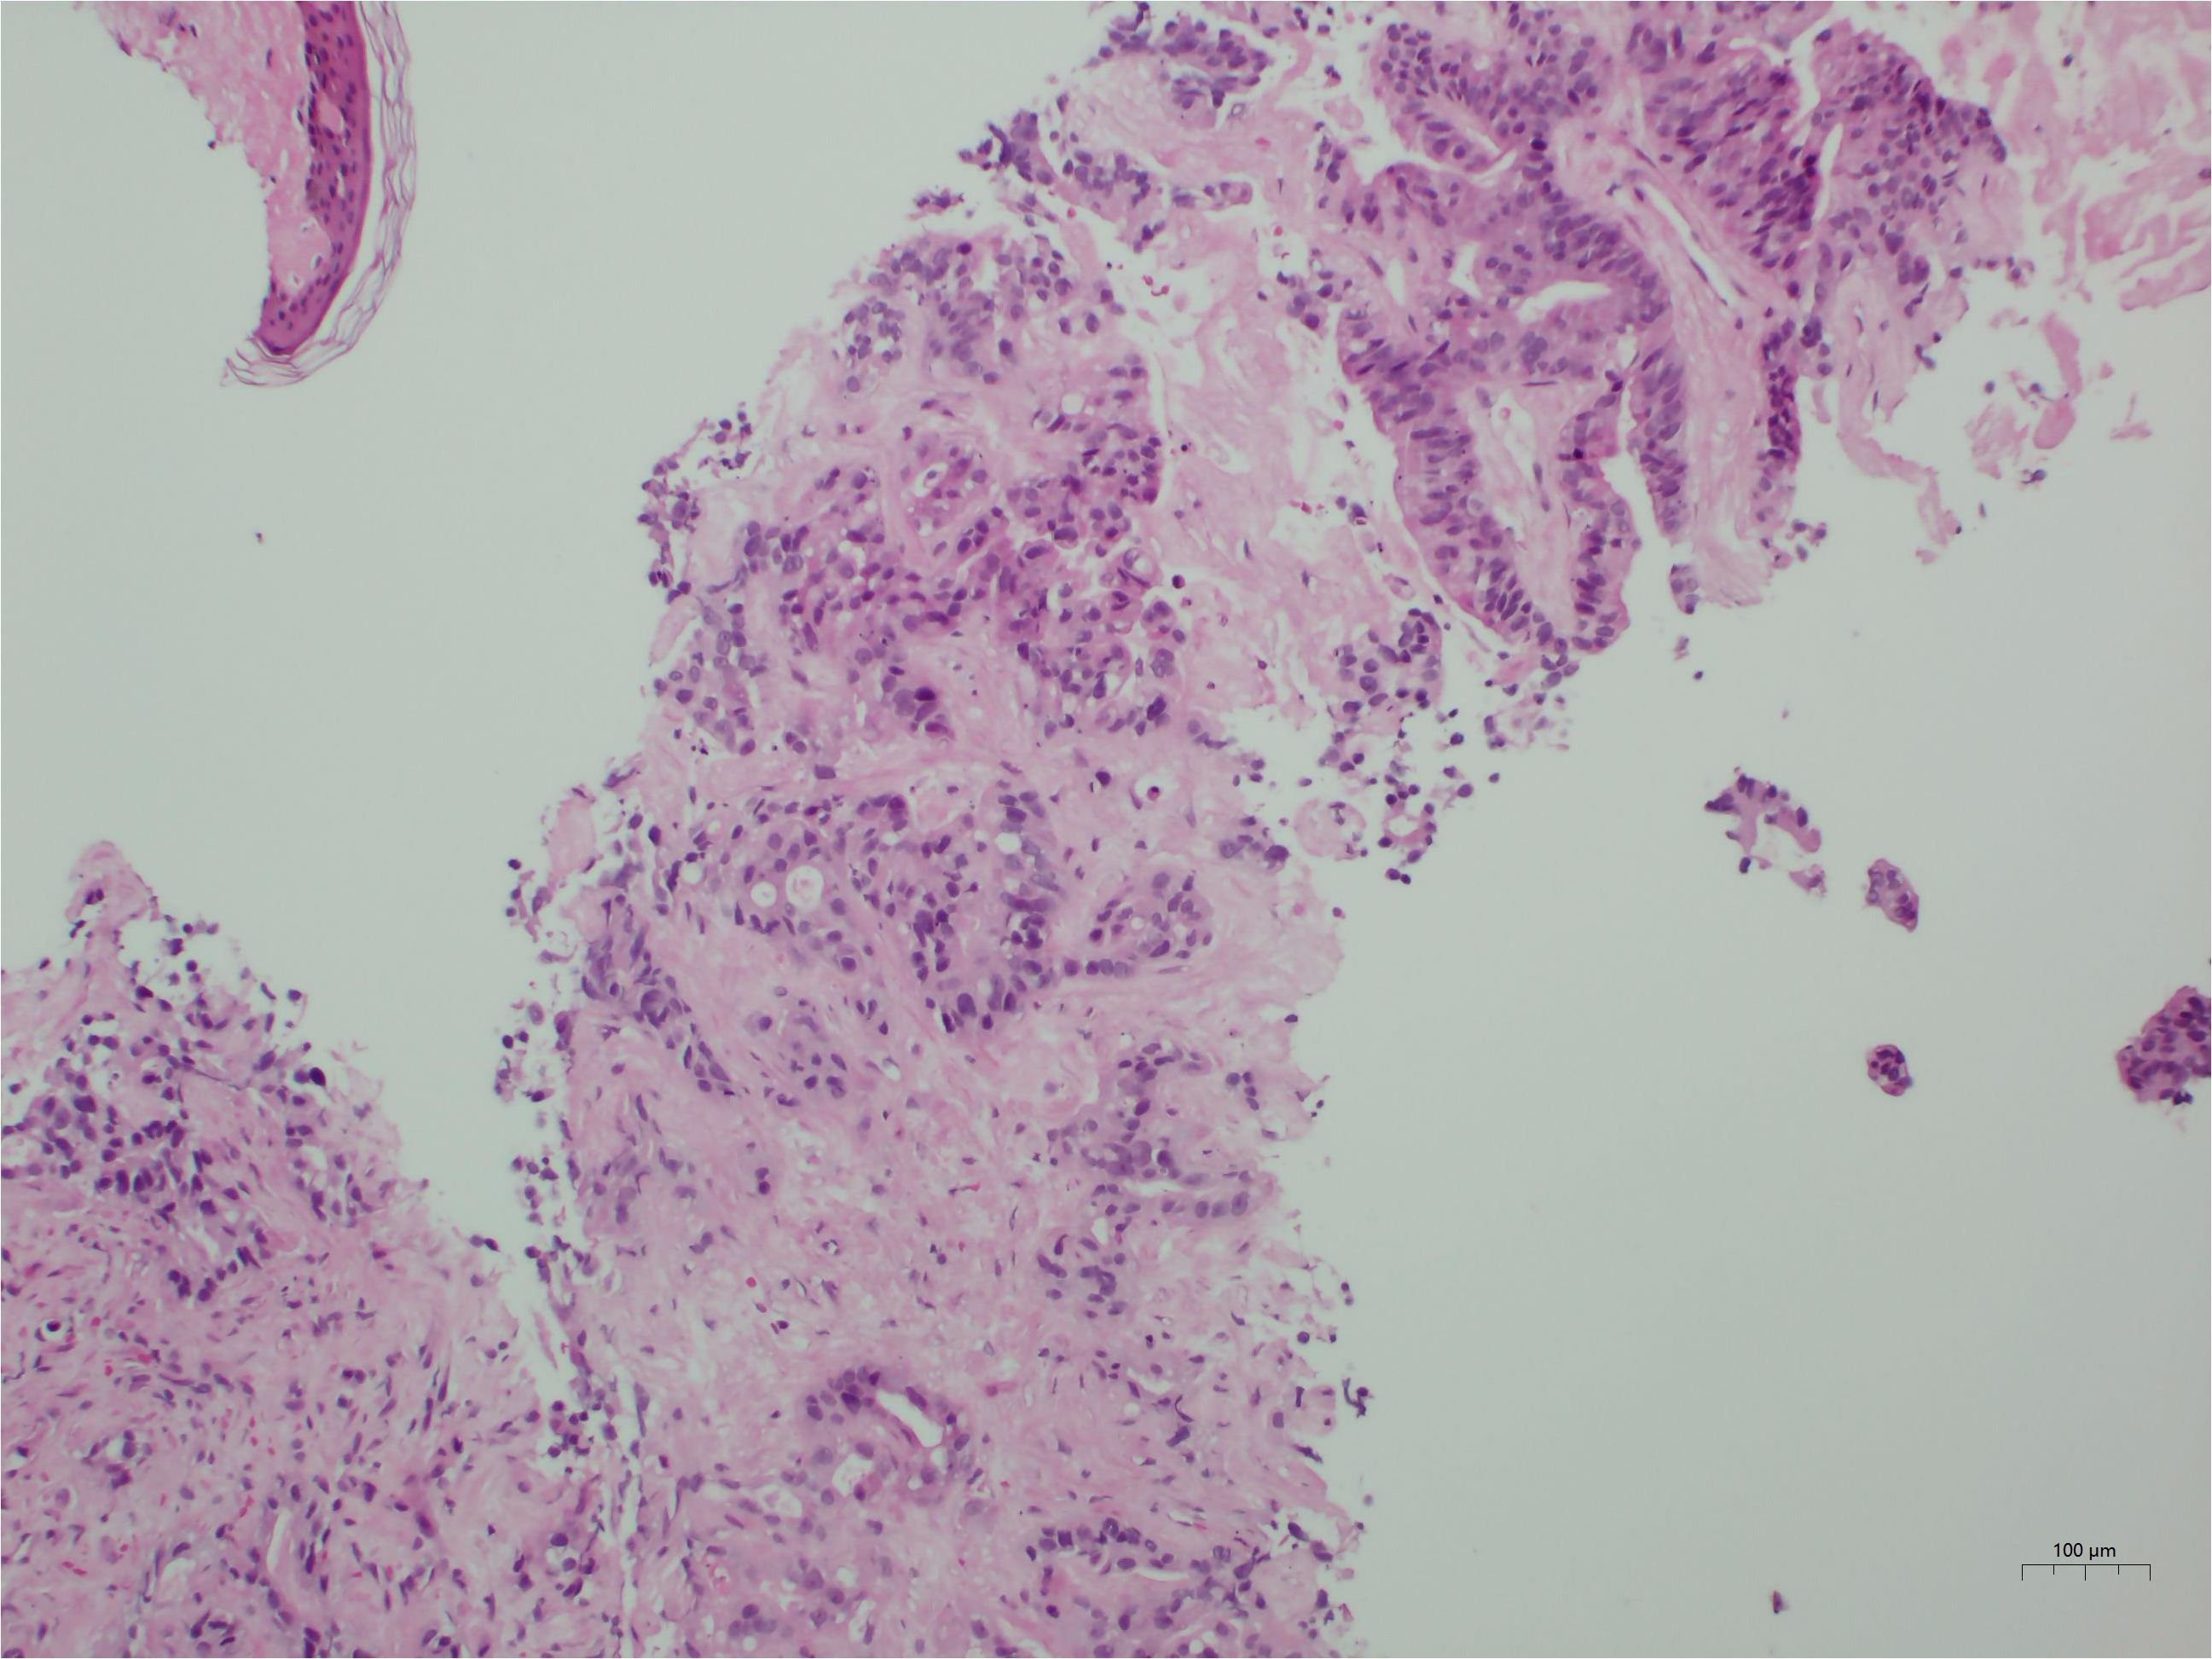

Background: Tumor lysis syndrome (TLS), characterized by electrolyte imbalances and acute kidney injury, predominantly occurs following cytotoxic chemotherapy in hematologic malignancies. Spontaneous TLS (STLS) in solid tumors remains rare. This report describes STLS induced by a diagnostic liver biopsy and reviews the literature on procedure-associated TLS. Case Presentation: An 84-year-old male presented with extensive hepatic metastases and markedly elevated tumor markers. Ultrasound-guided percutaneous liver biopsy confirmed the diagnosis of metastatic adenocarcinoma. Within 24 hours post-procedure, the patient developed acute respiratory failure, anuria, severe metabolic acidosis (pH 7.23), hyperkalemia (5.5 mmol/L), acute kidney injury (creatinine 299 μmol/L), hyperuricemia (716 μmol/L), and elevated lactate dehydrogenase (3953 U/L), fulfilling the diagnostic criteria for TLS. Concurrent hemothorax occurred. Continuous renal replacement therapy (CRRT) achieved rapid correction of metabolic derangements, with parameters returning to normal within seven days. Conclusion: Diagnostic liver biopsy can induce STLS in patients with high-burden solid tumors. Our systematic analysis reveals that minimally invasive procedures may precipitate TLS, emphasizing the importance of prophylactic measures, early recognition, and immediate CRRT initiation for optimal outcomes.